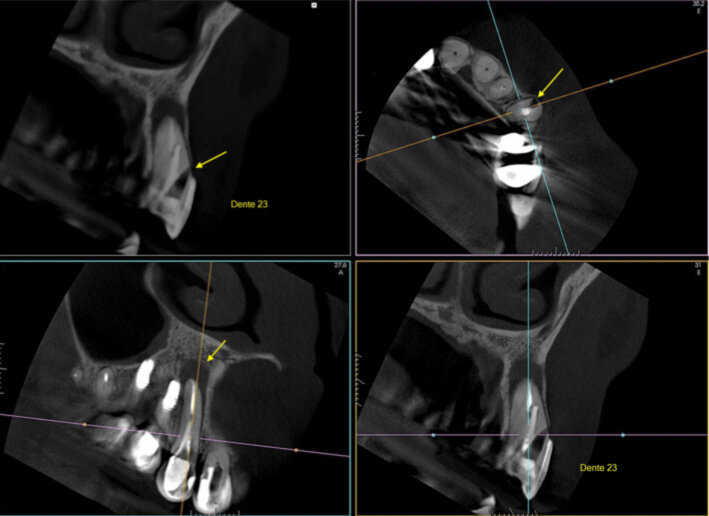

Fig. 1: A cone beam computed tomography was performed for diagnosis and to establish a treatment plan. (Photos/Provided by Renato Interliche, Douglas Giordani Negreiros Cortez and Clauber Romagnoli)

After clinical and radiographic examination, a cone beam computed tomography was performed for better diagnosis and to establish the treatment plan for the involved tooth (Fig 1).